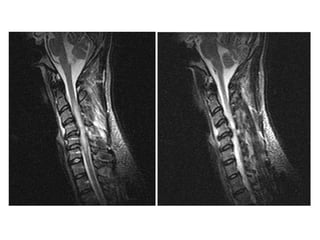

Background  Cervical spondylotic myelopathy (CSM) is a common cause of spinal dysfunction in the elderly.  It appears to occur in a much younger age group in Nigeria.  However it is frequently not diagnosed early due to the paucity of MRI scans. When diagnosed, many are treated with  steroids  and conservatively. Therefore, patients present late for surgical intervention.

Objectives We present a review of patients with cervical spondylotic myelopathy.  The early results of surgical management in 6 patients are presented to highlight the safety of operative intervention.

Case based discussions:  68 year old female, Hypertensive and Diabetic. Diabetes is poorly controlled. She presented with 6 months of progressive numbness in the hands and feet. Glove and stocking distribution. There are no other symptoms. Clinically, she has no motor deficits in all 4 limbs but has hyper reflexia. Objective sensory change was mostly in C7/C8 dermatomes bilaterally. Bowel and bladder function and walking were satisfactory.

MRI SCAN SAGITTAL T2W

Surgery performed was an anterior cervical discectomy and fusion using the patients’ iliac bone.  I decided to fuse at two levels C4/C5 and C5/C6 though the main focus was really to do a good decompression of the space behind the C5/C6 disc, which is the site of maximal compression on the MRI scan.